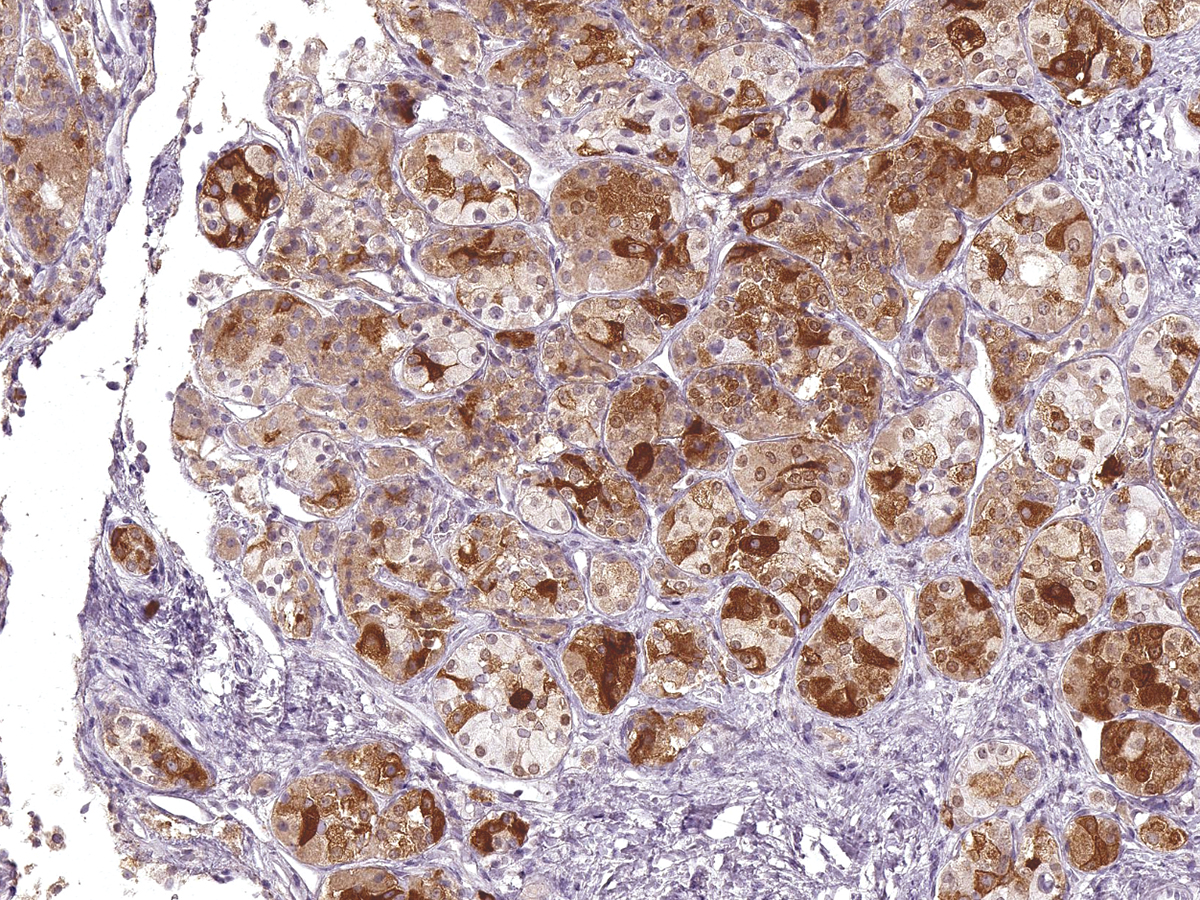

图片:

FSH [P1043] on Pituitary Gland